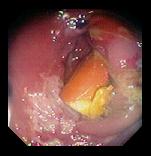

- На фото видны 13 капсул из общего количества, составившего 31 капсулу.

- 4-6. Различные случаи онаружения таблеток в кишечнике.